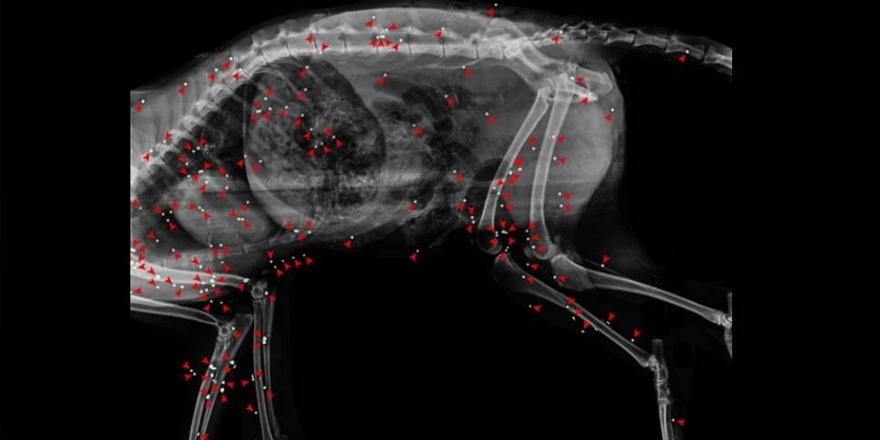

Taşkent Doğa Parkı, 06 Ocak 2024 tarihinde, bünyelerindeki Yaban Hayat Hastanesi’ne getirilen kızıl tilkinin, iki yüzden fazla saçmayla delik deşik edildiğini, omurgasının kırıldığını açıkladı. Taşkent Doğa Parkı’nın sosyal medya hesabından yapılan açıklamada, “Bugüne kadar karşılaştığımız vakalar arasında insan zulmünün en tüyler ürpertici örneklerinden bir tanesiydi” denildi.

Kızıl tilkiye ait olan röntgenin paylaşıldığı açıklamada, “Yüreklerimizi parçalayan bu zavallı yaratığın hikayesi, insanın doğa üzerindeki olumsuz etkisini, yarattığı doğa tahribatını ve insan olmayan canlıların korunmaya ne denli muhtaç olduğunu bir kez daha hatırlatıyor. Kendi haklarını savunamayanların haklarını savunmak hepimizin görevidir” ifadelerine yer verildi.

Bu yılın başlarında Yaban Hayat Hastane'mize getirilen bir hastanın hikayesi, bugüne kadar karşılaştığımız vakalar arasında insan zulmünün en tüyler ürpertici örneklerinden bir tanesiydi. 6 Ocak 2024 tarihinde, Lapta’dan tedavi tesislerimize bir Kızıl Tilki (Vulpes vulpes) ölü olarak ulaştırıldı. Röntgen sonuçlarının ardından hayvanın vücudunun 200’den fazla saçmayla delik deşik edildiği belirlendi. Ayrıca hayvanın omurgasında da kırıklar tespit edildi. Tilkinin başına gelenleri düşündüğümüzde gerçekten duygularımızı kelimelerle ifade etmekte zorlanıyoruz.